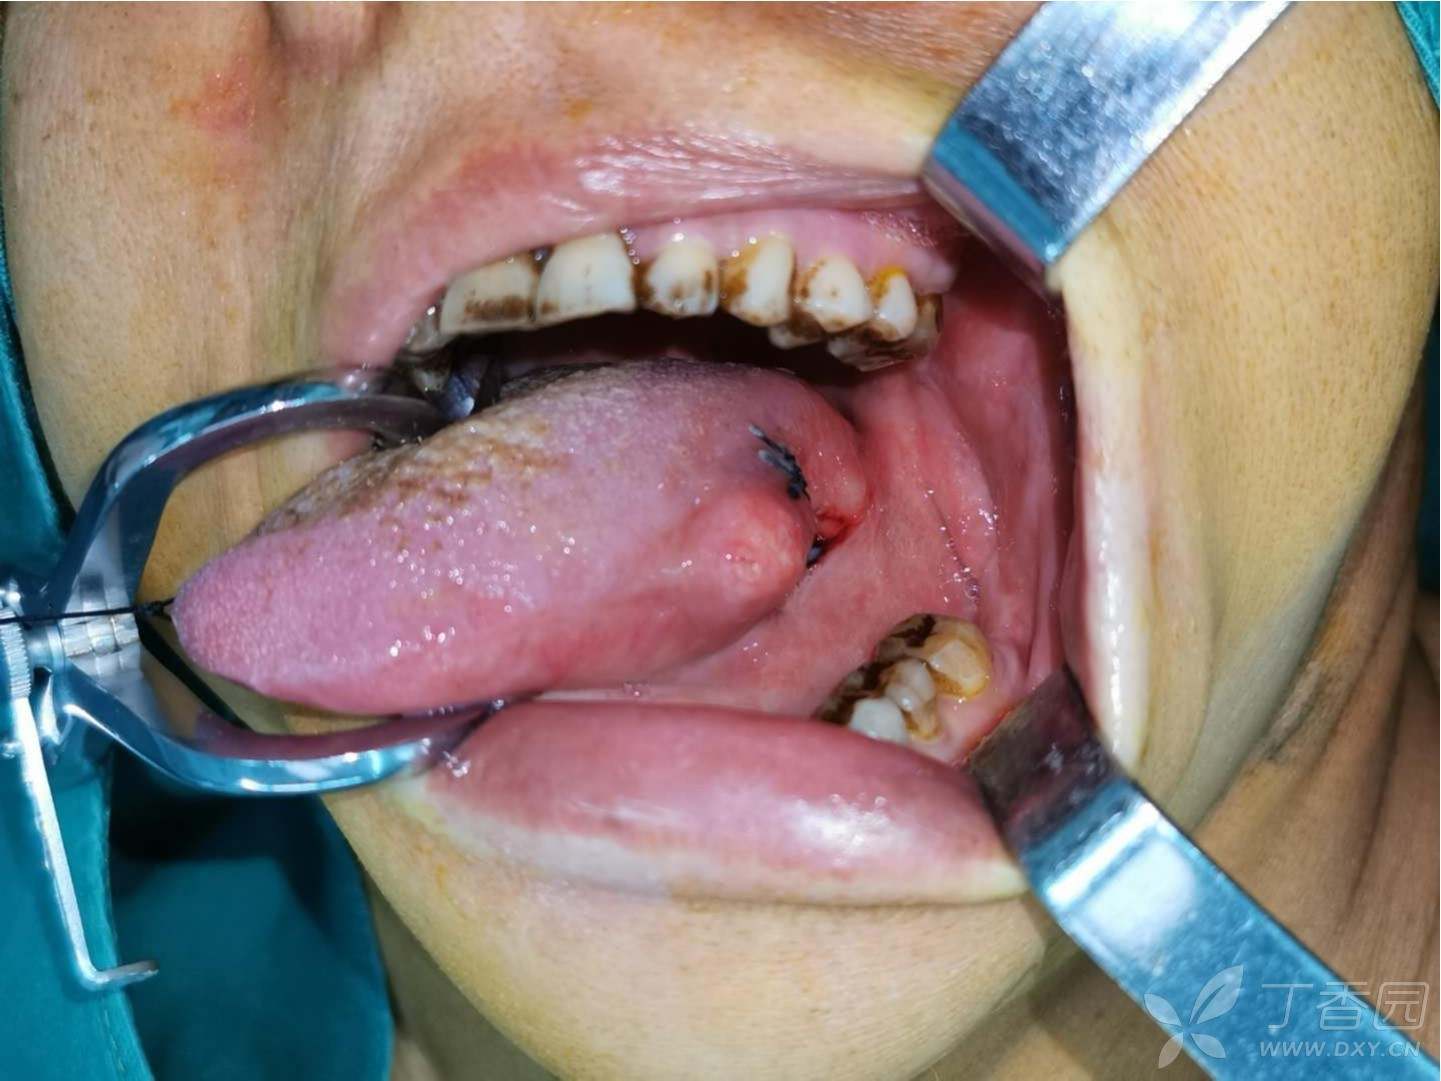

今天做的舌癌手术